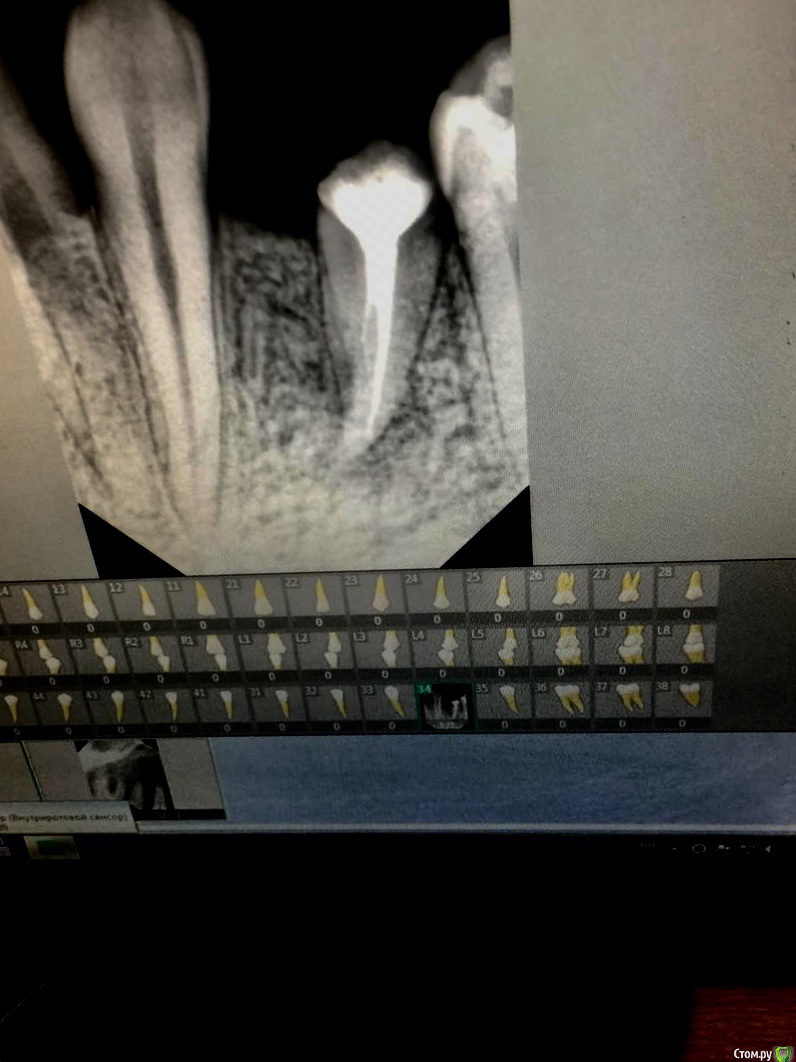

khelsa Опубликовано 20 августа, 2020 Поделиться Опубликовано 20 августа, 2020 Лечил зуб без снимка , потом увидел , что пропустил канал и не дошёл до верхушки зуба. Также обнаружил очаг костной деструкции. Стоит ли пытаться ещё раз попробовать перелить зуб ?не ругайте, только начал заниматься эндодонтией Ссылка на комментарий

khelsa Опубликовано 20 августа, 2020 Автор Поделиться Опубликовано 20 августа, 2020 Опечатка вышла , зуб 3.4 Ссылка на комментарий

Дмитрий Л. Опубликовано 20 августа, 2020 Поделиться Опубликовано 20 августа, 2020 По-моему там ступенька. Ссылка на комментарий

khelsa Опубликовано 20 августа, 2020 Автор Поделиться Опубликовано 20 августа, 2020 По-моему там ступенька. Или даже перфорация . Я проходил 10 фалом и вроде выходил за верхушку по апексалокатору , а может сделал перфо и через него и показывал апекс . Ссылка на комментарий

khelsa Опубликовано 20 августа, 2020 Автор Поделиться Опубликовано 20 августа, 2020 По-моему там ступенька. Хотя я сильно грубую силу не применял и осторожно пытался проходить Ссылка на комментарий

Дмитрий Л. Опубликовано 20 августа, 2020 Поделиться Опубликовано 20 августа, 2020 Хорошие мягкие файлы тонкие для первичного прохождения, с аплоком, при упоре сразу рентген, ирригация, после ковровой рсботайте ротационными по определённой длине. У вас нету клинического понимания, картина периодонтита может и 5 лет сохранятся после качественного эндо, решение ещё и на основании жалоб принимается.Здесь вопрос в том зачем было сделано эндо. На сколько функционален данный зуб? Будет ли он учавствовать в акте жевания? Можно ли изготовить коронку которая будет высотою в корень? Как бы там ни было, вы молодец, раз интересуетесь. 1 Ссылка на комментарий